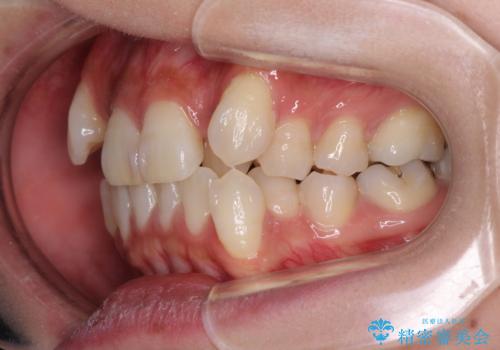

- 八重歯や前歯のデコボコを気にして来院された患者様です。

目立たない装置を希望されたので、上顎が裏側装置のハーフリンガルを選択し、上下左右の小臼歯(計4歯)を抜歯して矯正治療を行うこととしました。

補助装置を併用することで、八重歯を速やかに改善し、治療期間の短縮を図ることとしました。